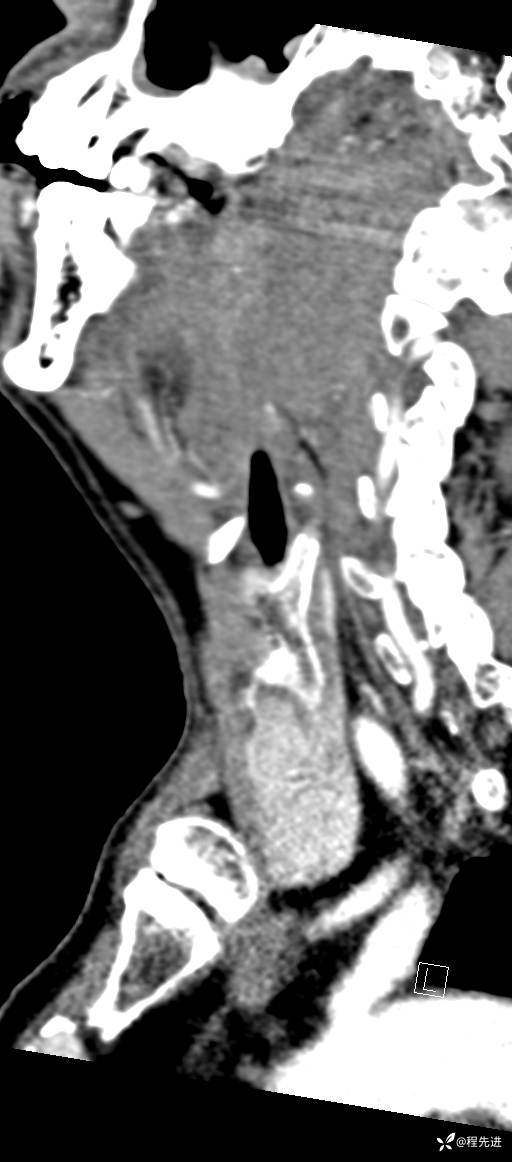

CT平扫:

CT增强:

动脉期:

增强冠矢状位重建:

CTA: